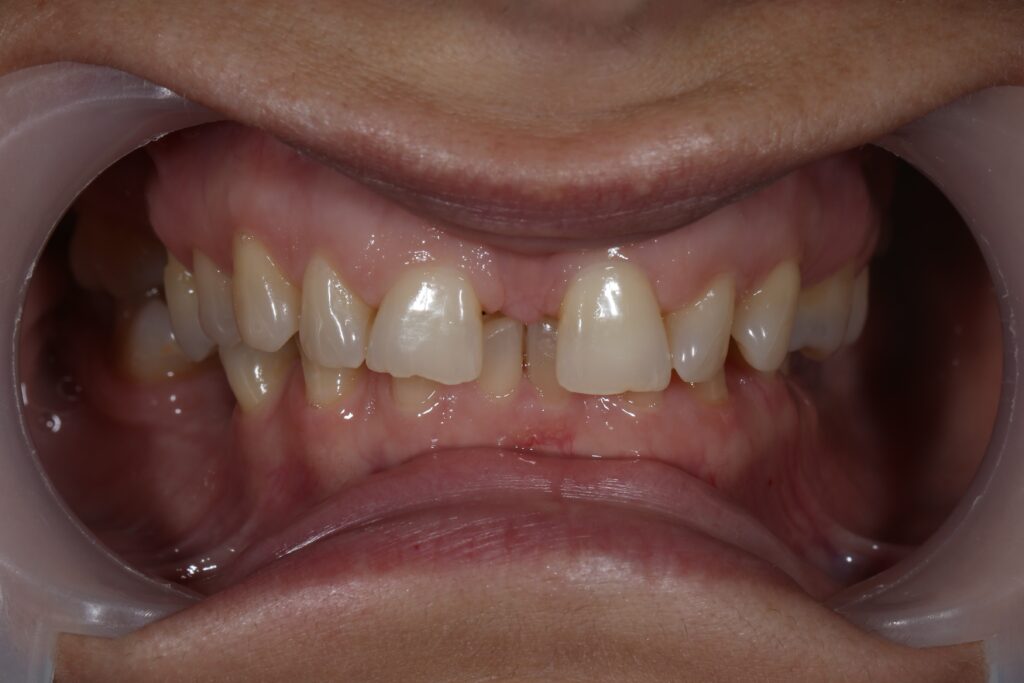

Результаты ортодонтической части

Была установлена брекет-система Damon Q. Срок лечения брекетами составил 11 месяцев.